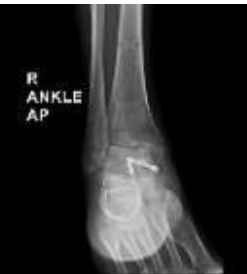

Total Talus Replacement using a Custom 3D-Printed Titanium Implant for Post-Traumatic Avascular Necrosis of Talus following Failed Internal fixation: A Case Report

Fatima Heba Habeeb , Ashish Varanasi , Lokesh Kumar Gupta , Yadlapalli Venkatesh , Sunil Dachepalli , Pradeep Moonot

………………………………p.292-296